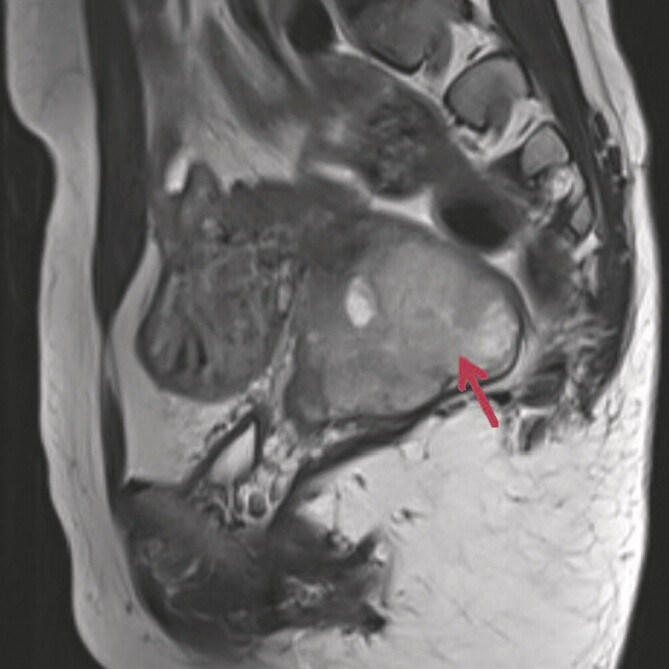

Abstract Image